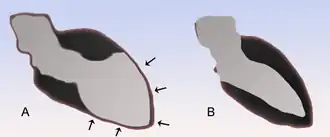

Geschichte

Das Krankheitsbild wurde 1991 erstmals beschrieben, Namensgeber war eine japanische Tintenfischfalle in Form eines Kruges mit kurzem Hals (Tako-Tsubo,[3][4] s. Abbildung). Die daran erinnernde eigentümliche Form der linken Herzkammer (linker Ventrikel) am Ende der Systole wurde von den Erstautoren als Folge einer Durchblutungsstörung des Herzmuskels angesehen, verursacht durch die krampfartige Verengung mehrerer Herzkranzgefäße (Koronarspasmen).[5]

A Stress-Kardiomyopathie

B Normalperson

Die Röntgenaufnahme der Thoraxorgane ist unauffällig oder zeigt eine sogenannte Lungenstauung („Wasser in der Lunge“) als Folge der Herzinsuffizienz. Bei der Echokardiografie ist die für das Tako-Tsubo-Syndrom typische Bewegungsstörung (Kontraktionsstörung) der linken Herzkammer oft nachweisbar, das apical ballooning. Diese auch bei der Laevokardiografie im Rahmen einer Herzkatheteruntersuchung nachweisbare Kontraktionsstörung des linken Ventrikels macht sich als oft eindrucksvolle Unbeweglichkeit (Akinesie) oder gar als paradoxe Beweglichkeit (Dyskinesie) der Herzspitze bemerkbar, die Ähnlichkeit mit einem Aneurysma aufweisen kann.

Im Unterschied zum Herzinfarkt ist allerdings bei der Koronarangiografie keine Verstopfung der Herzkranzgefäße nachweisbar. Erst dieser Befund der Herzkatheteruntersuchung erlaubt die zuverlässige Abgrenzung zum Herzinfarkt.